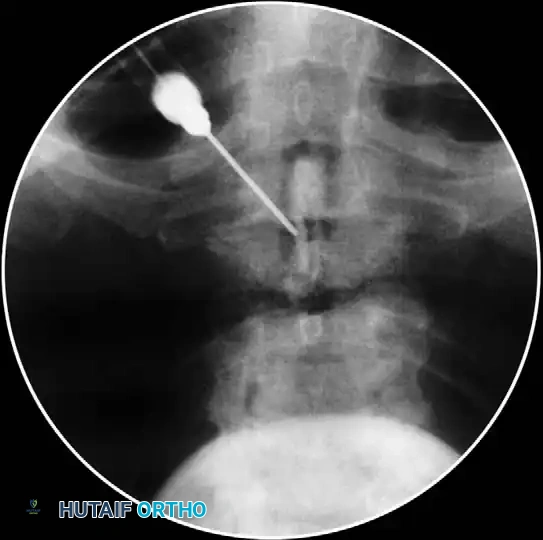

3. Localization: Using anteroposterior (AP) fluoroscopic imaging, identify the target laminar interspace.

5. Needle Insertion: Nick the skin with an 18-gauge hypodermic needle. Under continuous AP fluoroscopic control, advance a 22-gauge, 3 ½-inch spinal needle vertically until contact is made with the upper edge of the T1 lamina, 1 to 2 mm lateral to the midline. Anesthetize the periosteum and soft tissue tract upon withdrawal.

- Aspiration and Contrast: Aspirate to ensure no CSF or blood return. Attach a 5-mL syringe containing 1.5 mL of nonionic contrast dye (e.g., Iohexol).

- Epidurogram Confirmation: Inject the contrast under live fluoroscopy to produce an epidurogram. Adjust the C-arm to a lateral perspective to definitively document posterior epidural spread and rule out intrathecal or intravascular flow.

1. Oblique Fluoroscopy: The C-arm is rotated to an ipsilateral oblique angle (typically 15-25 degrees) to visualize the "Scotty Dog" anatomy. The target is the "safe triangle" located just inferior to the pedicle (the "eye" of the Scotty Dog) and superior to the exiting nerve root.

2. Needle Placement: A 22-gauge or 25-gauge spinal needle is advanced down the beam of the fluoroscope until the tip rests in the 6 o'clock position relative to the pedicle.

3. Lateral Confirmation: The C-arm is rotated to a true lateral view to ensure the needle tip is in the superior-anterior aspect of the neuroforamen, avoiding dural puncture medially.

- Contrast Injection: Live fluoroscopy during contrast injection must demonstrate medial flow into the epidural space and lateral flow outlining the exiting spinal nerve.